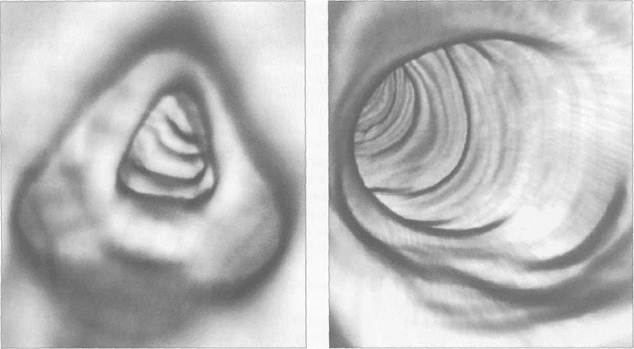

Рис. 11.38. КТ-колоноскопия. ЗБ-изображение поперечной ободочной кишки в норме.

Рис. 11.39. КТ-колоноскопия. ЗБ-изображение нисходящей ободочной кишки в норме.